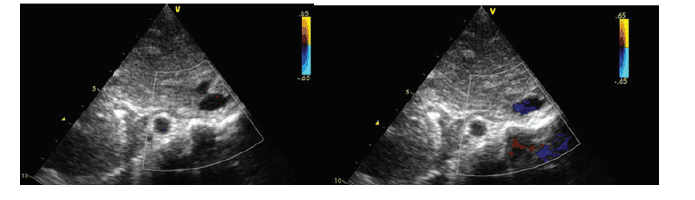

Considere a imagem ecocardiográfica obtida a seguir:

Podemos dizer que trata-se de: